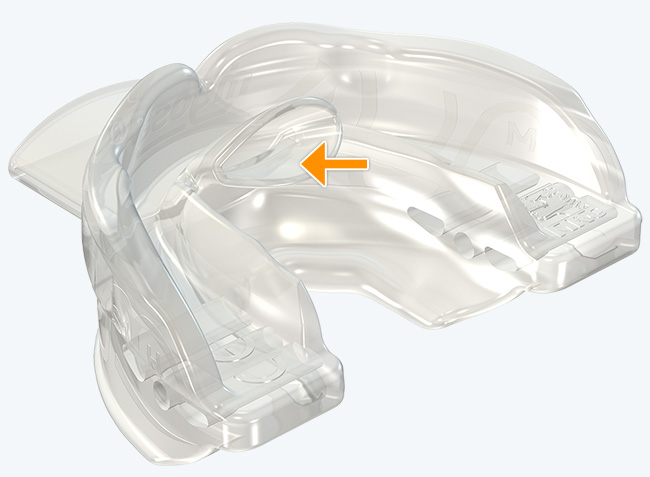

Myosa® for TMJBDS® Stage 1 Hybrid - S1H

Establish a functional airway and permits active exercises

The Myosa® for TMJBDS® S1H is specifically designed for patients who are breathing and disordered sleep (BDS) primary with moderate to severe BDS as indicated by a Breath Hold Time (BHT) of 20 or less. These patients may or may not have TMJ disorders, but due to the severity of their BDS, they require immediate improvement of their airway. The features of the appliance not only work to open the airway, but also allow patients to undertake initial exercising of the lip, tongue and airway muscles. Progress to the S1 when the patient’s BHT reaches 20 seconds or more.